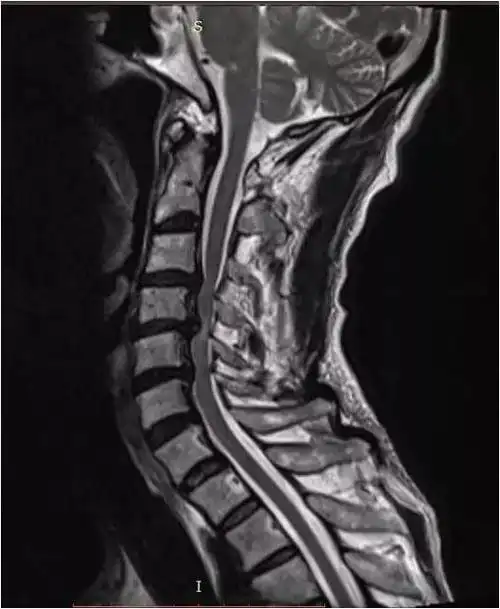

颈椎管狭窄前路还是后路